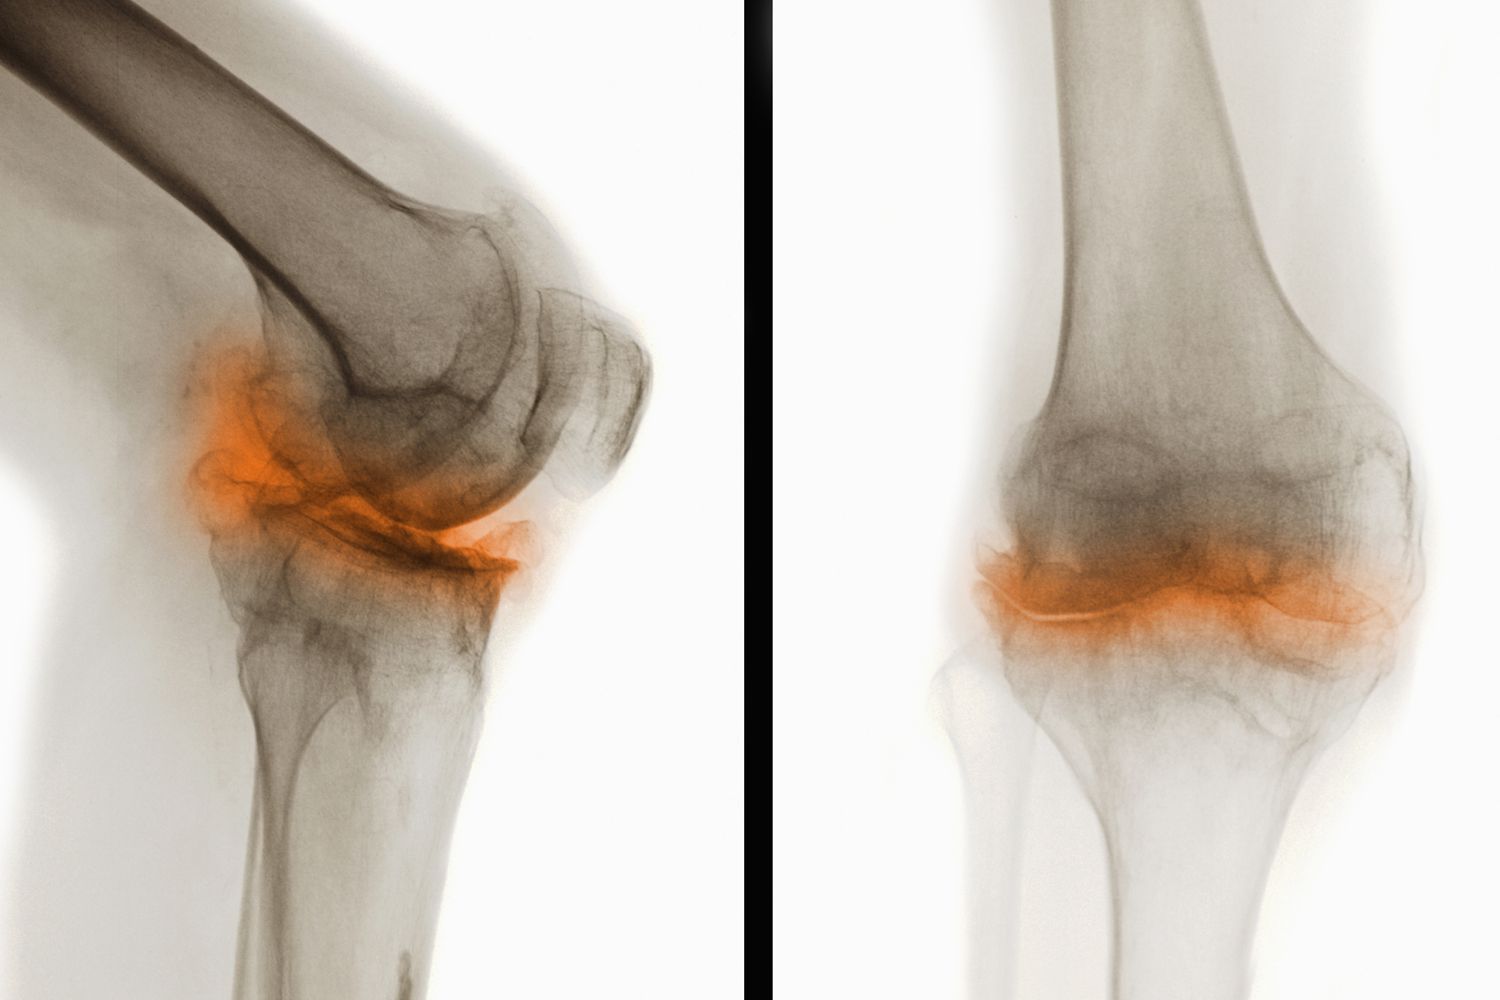

干細(xì)胞治療骨關(guān)節(jié)炎是一種新興且具有前景的治療方法。骨關(guān)節(jié)炎是一種常見(jiàn)的退行性關(guān)節(jié)疾病,主要表現(xiàn)為關(guān)節(jié)軟骨退化和骨質(zhì)增生,導(dǎo)致疼痛、僵硬和活動(dòng)受限等癥狀。干細(xì)胞治療通過(guò)利用干細(xì)胞的自我更新、多向分化和免疫調(diào)節(jié)能力,為骨關(guān)節(jié)炎患者帶來(lái)了新的希望。這也讓干細(xì)胞治療骨關(guān)節(jié)炎成為了研究的熱點(diǎn)。

骨關(guān)節(jié)炎(Osteoarthritis,簡(jiǎn)稱OA)是一種常見(jiàn)的慢性退行性關(guān)節(jié)疾病,主要表現(xiàn)為關(guān)節(jié)軟骨的退化和破壞,導(dǎo)致關(guān)節(jié)疼痛、僵硬和功能障礙。這種疾病通常發(fā)生在中老年人群中,尤其是負(fù)重較大的膝關(guān)節(jié)、髖關(guān)節(jié)、脊柱及遠(yuǎn)側(cè)指間關(guān)節(jié)等部位。